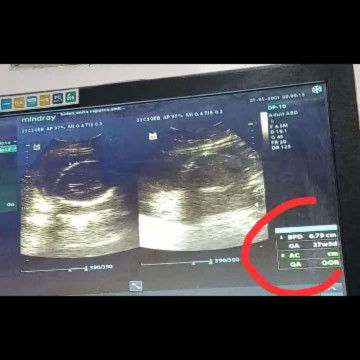

ketuban keruh 25week

Assalamualaikum bun, mau tanya usia khmilan aq 6bulan tp pas usg usia khmilan 27week dan brt janin 800gr apa kah wajar bun? Trus kalau ktuban keruh di usia sgini apa mash bisa brubah jernih lg bun ktubannya, gmn ya bun biar bersih lg ketubannya, terimakasih yang mau jawab🤗😊